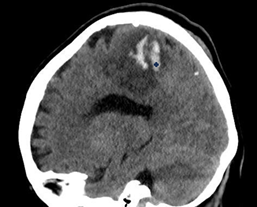

Sagittal

(Figure 3) and coronal (Figure 4) images of a single-phase

cranial tomography, showing the cashew sign (cashew nut).

Figure

3: Sagittal image of a single-phase cranial tomography, showing the cashew

sign (cashew nut)

4: Coronal image of a single-phase cranial tomography, showing the cashew